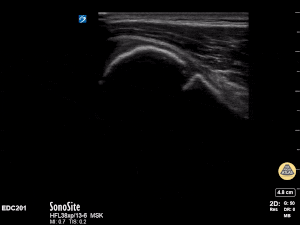

12y male presenting with RUE pain after bike injury. POCUS demonstrating proximal humeral fracture. Long axis and short axis views of fracture. Matthew Moake, MD PhD